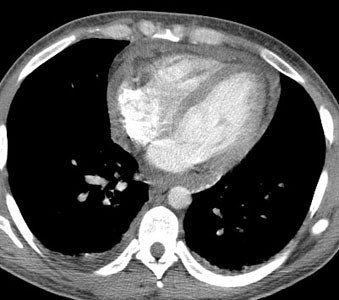

Myocarditis: This is a case of a patient with myocarditis. Note the intense cardiac gallium accumulation. Any inflammatory condition can result in increased gallium accumulation. CT scan demonstrated a small pericardial effusion. |